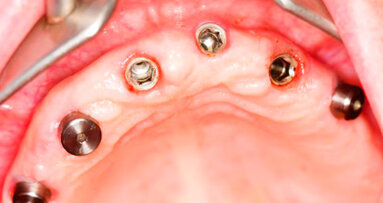

Roma, Italia: uno studio ha scoperto che gli impianti corti sono un’opzione di successo nei trattamenti a breve termine per le procedure ricostruttive in situazioni cliniche di limitata altezza verticale dell’osso. I ricercatori dell’Università di Roma hanno valutato in maniera sistematica gli studi clinici di impianti inferiori a 10 mm di lunghezza per determinare il successo di protesi supportate da impianti corti nei casi di mandibola atrofica.

Infine, i ricercatori hanno selezionato e analizzato due studi randomizzati e controllati e 14 studi osservazionali, indagando 6.193 impianti corti da 3.848 partecipanti. Hanno trovato una percentuale cumulativa di sopravvivenza del 99,1%, una percentuale di successo biologico del 98,8% e una percentuale di successo biomeccanico del 99,9%. Una più alta percentuale di sopravvivenza complessivo è stata segnalata per gli impianti con superficie ruvida.

I ricercatori hanno concluso che l’applicazione di protesi supportate da impianti corti nei pazienti con creste alveolari atrofiche sembra essere un’opzione di trattamento a breve termine di successo. Tuttavia, ritengono che siano necessari ulteriori studi scientifici per accertare se questa possa essere anche una valida opzione a lungo termine.

Negli ultimi anni sempre più autori si sono interessati all’utilizzo degli impianti corti, cioè di impianti di lunghezza pari o ...